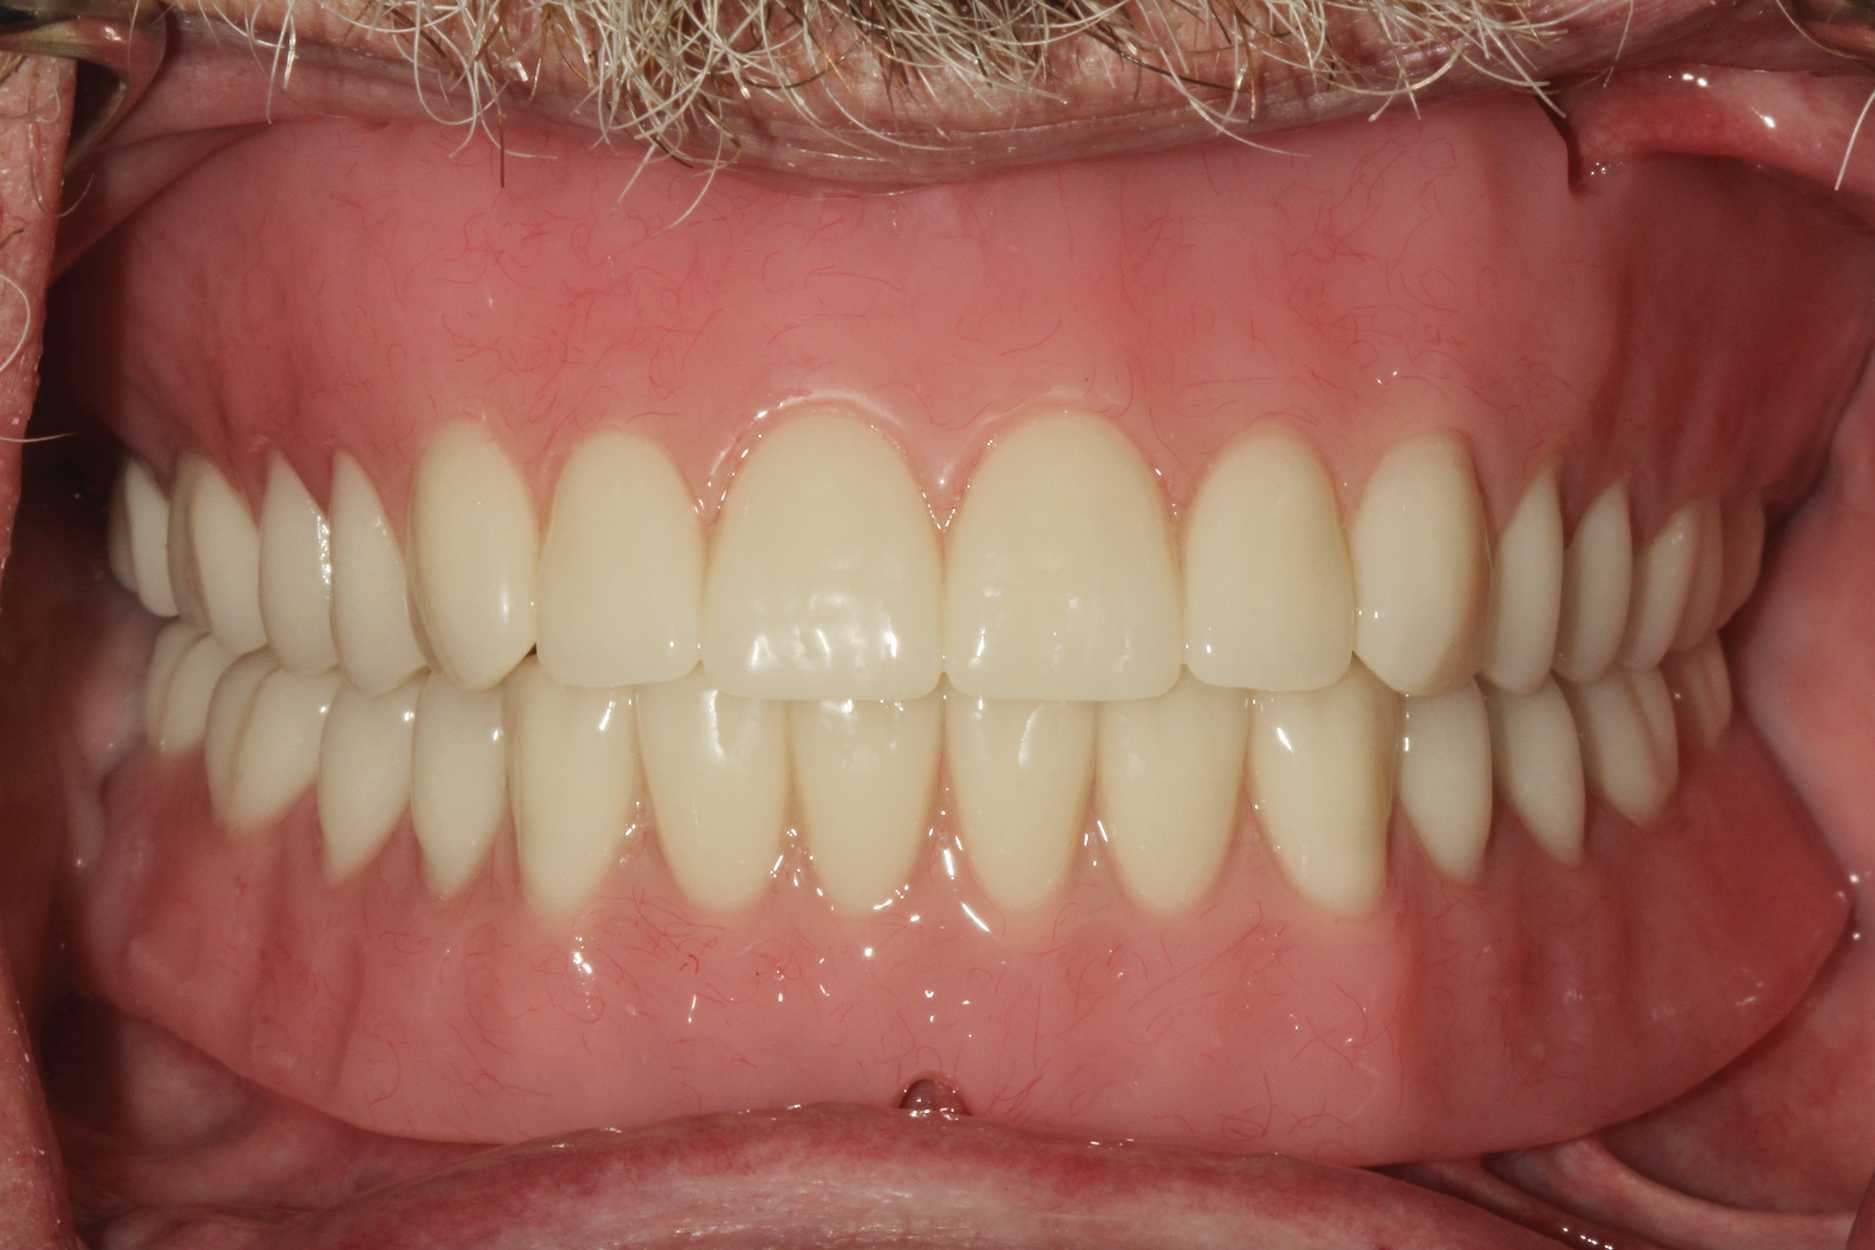

The patient returned for placement of the final prostheses. Housings were attached to the top of each of the abutments, and composite resin (CHAIRSIDE® Attachment Processing Material, Zest Dental Solutions, [alternatively: Quick Up®, Voco; Pattern Resin, GC America]) was placed into the recesses (Figure 10). The prostheses were seated onto the edentulous ridges, and housings were attached to the prostheses intraorally. After complete polymerization, the processing inserts were removed, and medium-strength nylon inserts were placed into the housings within the denture (Figure 11). The patient was given instructions on inserting and removing the prostheses and was satisfied with esthetics, fit, and form of the restorations (Figure 12).

Fig 12. At a follow-up appointment approximately 2 weeks post-treatment, the patient indicated he was satisfied with the esthetics, fit, function, and insertion/removal of the prostheses.

Figure 12